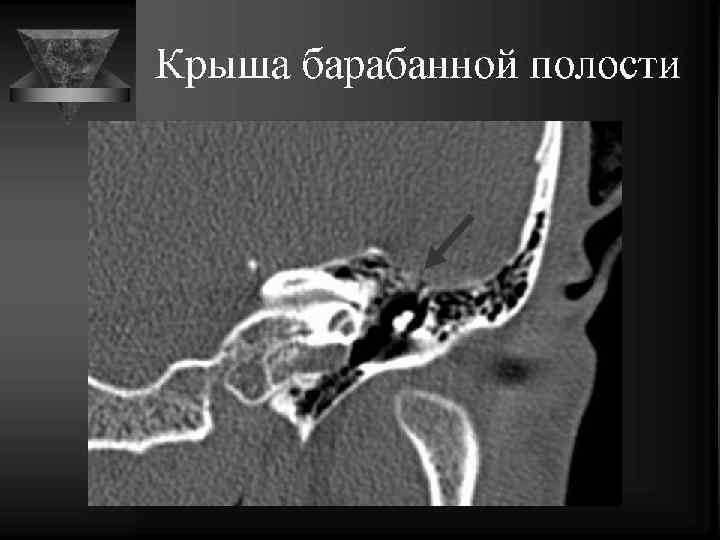

Среднее ухо • Содержимое: потеря воздушности. • Локализация и наличие патол. образований. • Слуховые косточки: вывих, деструкция, анкилоз. • Состояние круглого и овального окна. • Состояние горизонтальной части канала лицевого нерва. • Область расположения коленчатого ганглия. • Барабанная перепонка: утолщена, втянута. • Положение и контуры внутренней сонной артерии, сонного канала. • Положение яремной ямки, состояние луковицы внутренней яремной вены